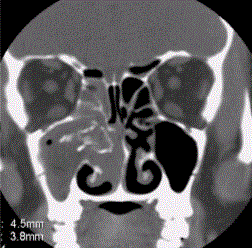

问题 患者男,35岁,鼻腔分泌物多,流脓涕,鼻塞,头痛,面部局部压痛1个月余。体检:鼻腔分泌物多,鼻黏膜肿胀。CT表现如下图。 上颌窦发生感染机会最高的原因是

选项 A.上颌窦最大 B.于鼻腔开口位于各鼻窦开口之下 C.窦腔开口位置高,窦底位置低 D.上颌窦发育早 E.引流差 F.上颌窦变异较多

答案 ABCDE